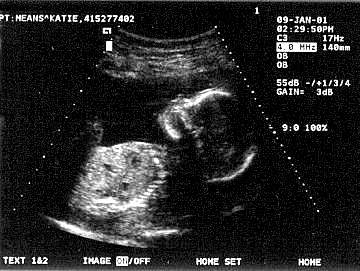

Looks just like me doesn't it